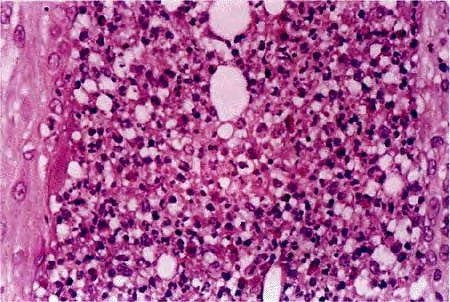

Eosinophilic fasciitis = التهاب الصفاق بالحمضات Eosinophilic Fasciitis Shulman’s Syndrome First described in 1974 , eosinophilic fasciitis is a scleroderma-like disorder characterized by inflammation and thickening of the deep fascia. It has a rapid onset associated with pain, swelling, and progressive induration of the skin leading to exaggerated deep grooving of the skin around superficial […]